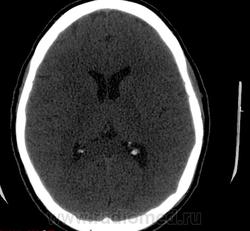

Прошу разрешить спор. По КТ - норма. Женщина, 1967г.р., жалобы на головную боль, больше в затылочной области. По-моему, не КТ-шное это дело но всеж...

Открыл. В мозгу ничего осбенного не увидел. По поводу Киари ничего не скажу, на аксиалах не вижу, а реконструкции эти срезы не строят Да и отношусь я к этой патологиии как к норме.

Аномалию Арнольда-Киари 1типа.

На МРТ выставили  аномалию Арнольда-Киари 1, нам сказали фу... На что я ответил, что по " ловцу и рыба". Во - первых, линию на КТ провести сложно ( в данном иссл.), во-вторых - естественные артефакты костей основания. И вообще пошли на...МРТ! Но осадок остался.

Для Арнольда-Киари I МРТ - как раз и есть метод диагностики, а на КТ это дело можно лишь заподозрить. Плюньте на осадок. Ну хотите, я плюну?) Тока отойдите, а то разъест))).